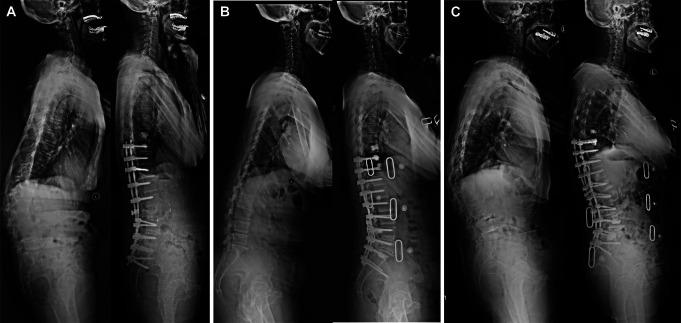

The Scoliosis Research Society (SRS)-Schwab system does not include a pelvic compensation (PC) subtype, potentially contributing to gaps in clinical characteristics and treatment strategy for deformity correction. It also remains uncertain as to whether PC has differing roles in sagittal balance (SB) or imbalance (SI) status. To compare radiological parameters and SRS-22r domains between patients with failed pelvic compensation (FPC) and successful pelvic compensation (SPC) based on preoperative SB and SI.

A total of 145 adult spinal deformity patients who received deformity correction were analyzed. Radiographic and clinical outcomes were collected for statistical analysis. Patients were classified into 4 groups based on the median value of PT/PI ratio (PTr) and the cutoff value of SB. Patients with low PTr and high PTr were defined as FPC and SPC, respectively. Radiographic and clinical characteristics of different groups were compared.

Patients with SPC exhibited significantly greater improvements in lumbar lordosis, pelvic tilt, PTr, and T1 pelvic angle as compared to patients with FPC, irrespective of SB or SI. No apparent differences in any of SRS-22r domains were observed at follow-up when comparing the SB-FPC and SB-SPC patients. However, patients with SI-SPC exhibited significantly better function, self-image, satisfaction, and subtotal domains at follow-up relative to those with SI-FPC. When SI-FPC and SI-SPC patients were subdivided further based on the degree of PI-LL by adjusting for age, the postoperative function and self-image domains were significantly better in the group with overcorrection of PI-LL than undercorrection of PI-LL in SI-FPC patients. However, no differences in these SRS-22r scores were observed when comparing the subgroups in SI-SPC patients.

Flexible pelvic rotation is associated with benefits to the correction of sagittal parameters, irrespective of preoperative SB or SI status. However, PC is only significantly associated with clinical outcomes under SI. Patients with SI-FPC exhibit poorer postoperative clinical outcomes, which should be recommended to minimize PI-LL.